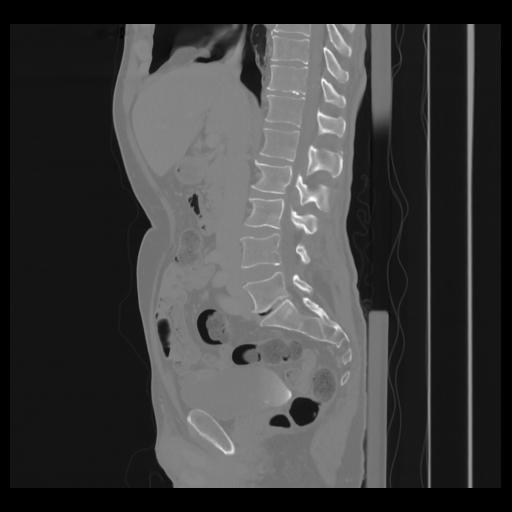

36 CUERPO,CE,Sagittal,3.000,CUERPO,Sagittal,